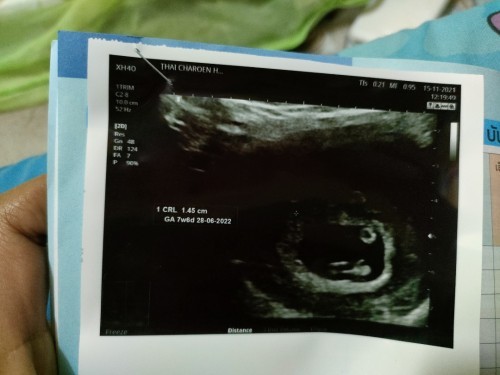

อัลตร้าซาวด์ครั้งแรกเหมือนเห็นเป็น2คน(รูปแรก)...ผ่านไป1อาทิตย์คุณหมอนัดไปอัลตร้าซาวด์ใหม่แต่เห็นคนเดียว(รูปที่2)...แม่ๆคิดว่าไงคะ...หมอนัดอีกครั้งหน้าก็วันที่10เดือนมกราคม65

เหมือนมี 2 คนจริงๆ ค่ะ